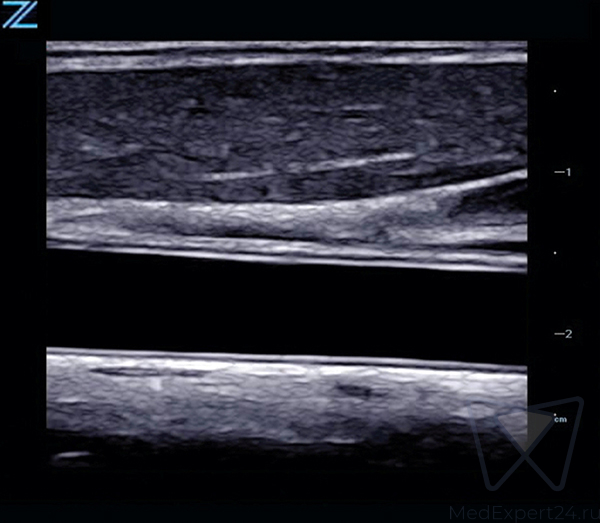

Система Zonare ZS3 оснащена инновационной программной технологией ZONE Sonography Technology (ZST), обеспечивающей диагностические преимущества в любых клинических ситуациях. Сфокусированное по всей глубине сканирования, четкое и детализированное изображение в В-режиме в сочетании с визуализацией в доплеровском режиме, позволяют охватить весь спектр клинических потребностей. УЗИ аппарат премиум класса подходит для проведения качественных исследований в любых условиях, благодаря быстрому переключению режимов и эргономичной, легкой портативной конструкции.

- Непревзойденное качество визуализации для выполнения различных исследований,